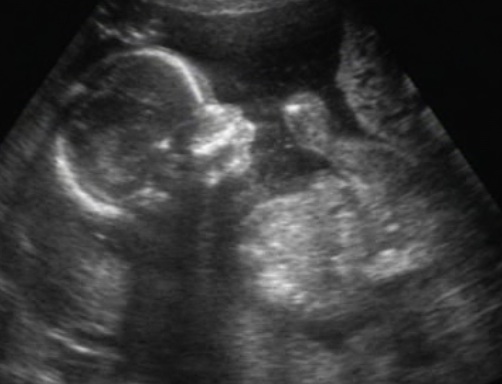

Hoztam én is képeket :P Profilból, ásítós, tappancsos na meg a bizonyíték, hogy kisfiú :wink:

Kép